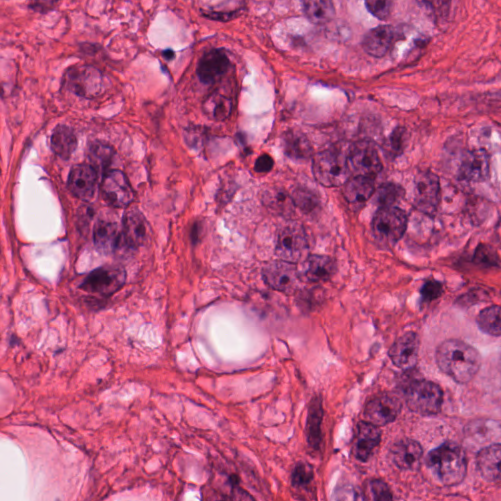

As an essential part of digital pathology, histopathology image analysis is playing increasingly important role in cancer diagnosis, which can provide direct and reliable evidence to diagnose the grade and type of cancer. This paper deals with nuclei segmentation, an important step in histopathological image analysis. The purpose of nuclei semgentation is not only counting the number of nuclei but also obtaining the detailed information of each nucleus. So unlike nuclei detection, here the outputs are the contour of each nucleus instead of only the position of their central points. Hence we can exactly extract each nucleus from the image and make it available for further analysis. For example, the features of the individual nucleus and the distribution of nuclei clusters can be used to grade and classify status of breast cancers [3, 4]. Because of appearance variation such as color, shape, and texture, nuclei segmentation from histopathological images could be very challenging, as illustrated in Fig.1, in which it is very challenging even for human to recognize and segment all nuclei within the images. Fig.1(a) and Fig.1(b) illustrate two histopathological images from different organs. Fig.1(c) and Fig.1(d) are two histopathological images from same organ but have different cancer grade.

Figure 1: (a)Colon cancer (b)Prostate cancer (c)Breast cancer (grade I) (d)Breast cancer(grade III)